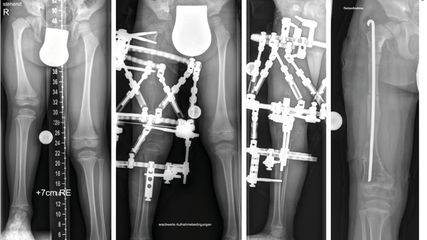

Angeborene Fehlstellungen des Unterschenkels

Kongenitale Deformitäten des Unterschenkels gehören zu den seltenen, aber medizinisch bedeutenden und operativ herausfordernden Diagnosen der Kinderorthopädie. Eine differenzierte ...